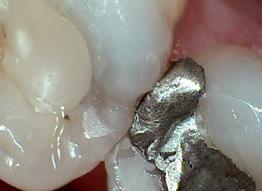

by Larry M. Guzzardo

The process of moving a patient from one member of the team to another is called a “hand-off.” We do this by never leaving a patient alone without letting them know who and what to expect next. It means you never leave them alone in a treatment room, wondering who’ll come in next or how long they will be there, or you never drop them off at the front desk to talk to a receptionist on the phone. It requires informing your patient of each step of the way by explaining who and what comes next, anticipating their needs, and introducing them to the next team member, all while creating an environment that will increase treatment acceptance and reduce canceled and broken appointments.

That’s why I propose that the patient experience multiple hand-offs throughout their visits. Consider how many times this can happen. The patient needs to be handed off by the dentist to his or her dental assistant. The dental assistant then needs to hand-off the patient perfectly to the front office person, who then also needs to clear everything up with the patient again.

The hand-off that helps a patient connect:

Of course, in each hand-off, the patient must be included. Every time a patient hears the information passed on in the hand-off, a little more sinks into their mind. I find that dental office hand-offs are not long enough and do not involve enough people. This brevity is what creates confusion for the patient. How often do we see that the front-desk hand-offs can be so brief they’re almost curt? For example, “We need a 30-minute appointment for a DO on 17.”

And sadly, I often hear this in clinical areas as well. The dentist will simply tell their assistant what is needed next without including the patient in the exchange. So, now we have a patient with little or no commitment to their treatment. There are no “dots” to connect yet; it

only takes a few seconds more to explain the next step.

This is what should happen to help patients “connect the dots”: The dentist should be communicating with the patient throughout the appointment about what they are doing, why they are doing it, and how things are progressing. At the end of the appointment, as the chair is brought up, the dentist must take command by coming around to the front of the chair, connect with the patient by making eye-to-eye contact, and take the following 10 steps: